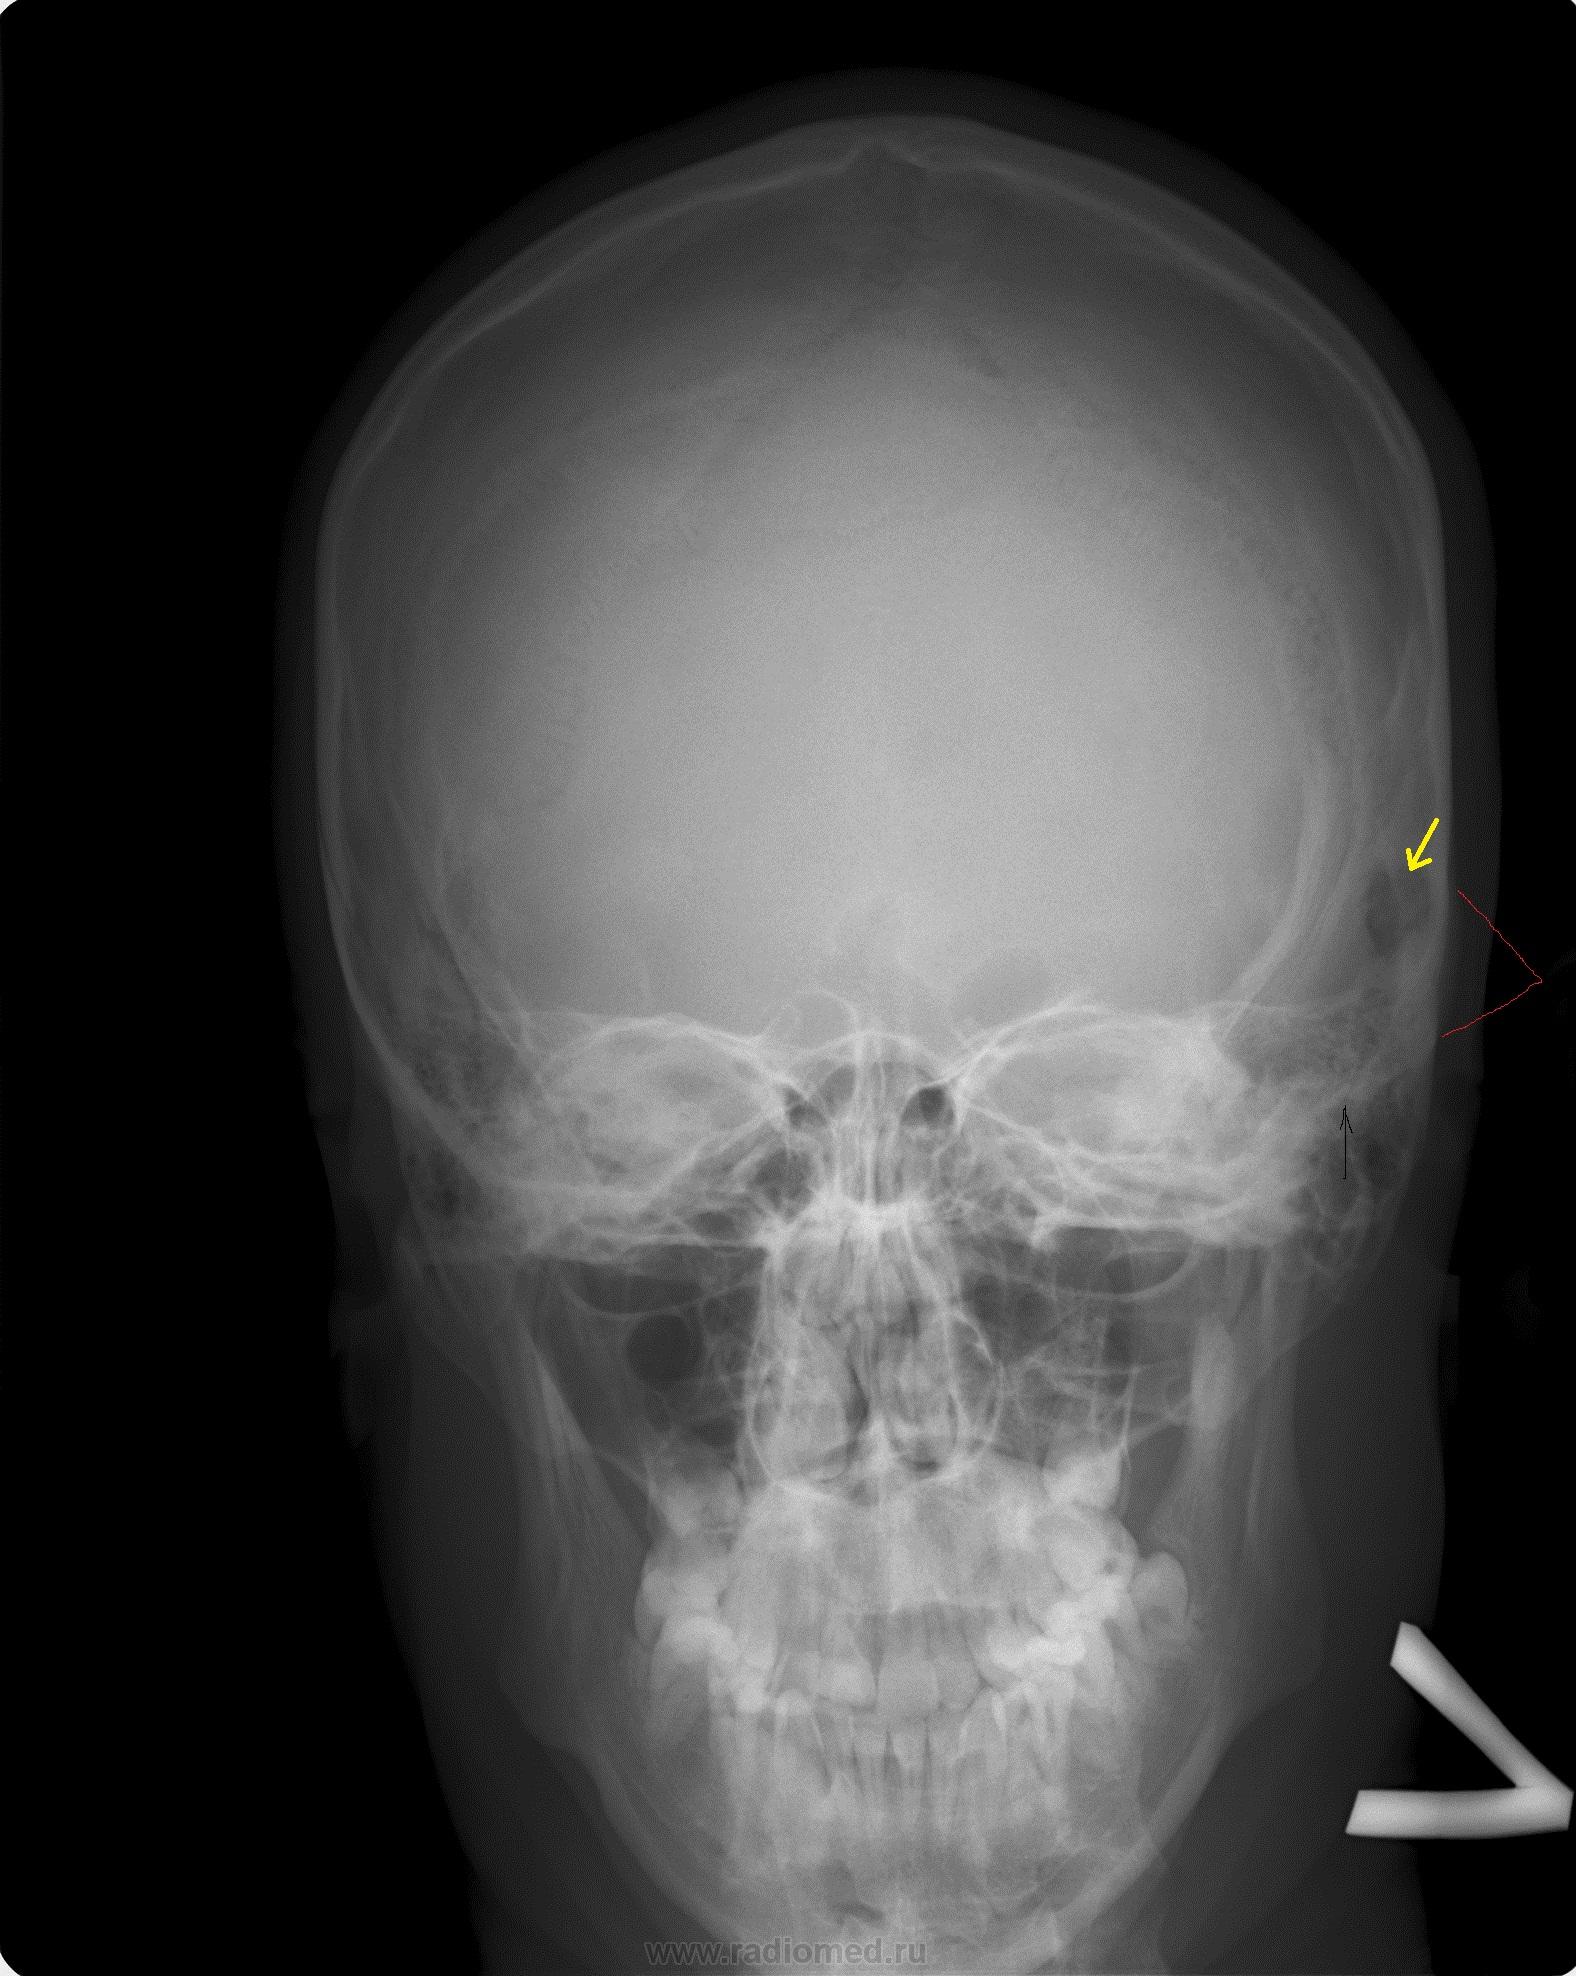

Анатомия детского черепа: Рентгеновские снимки и описание